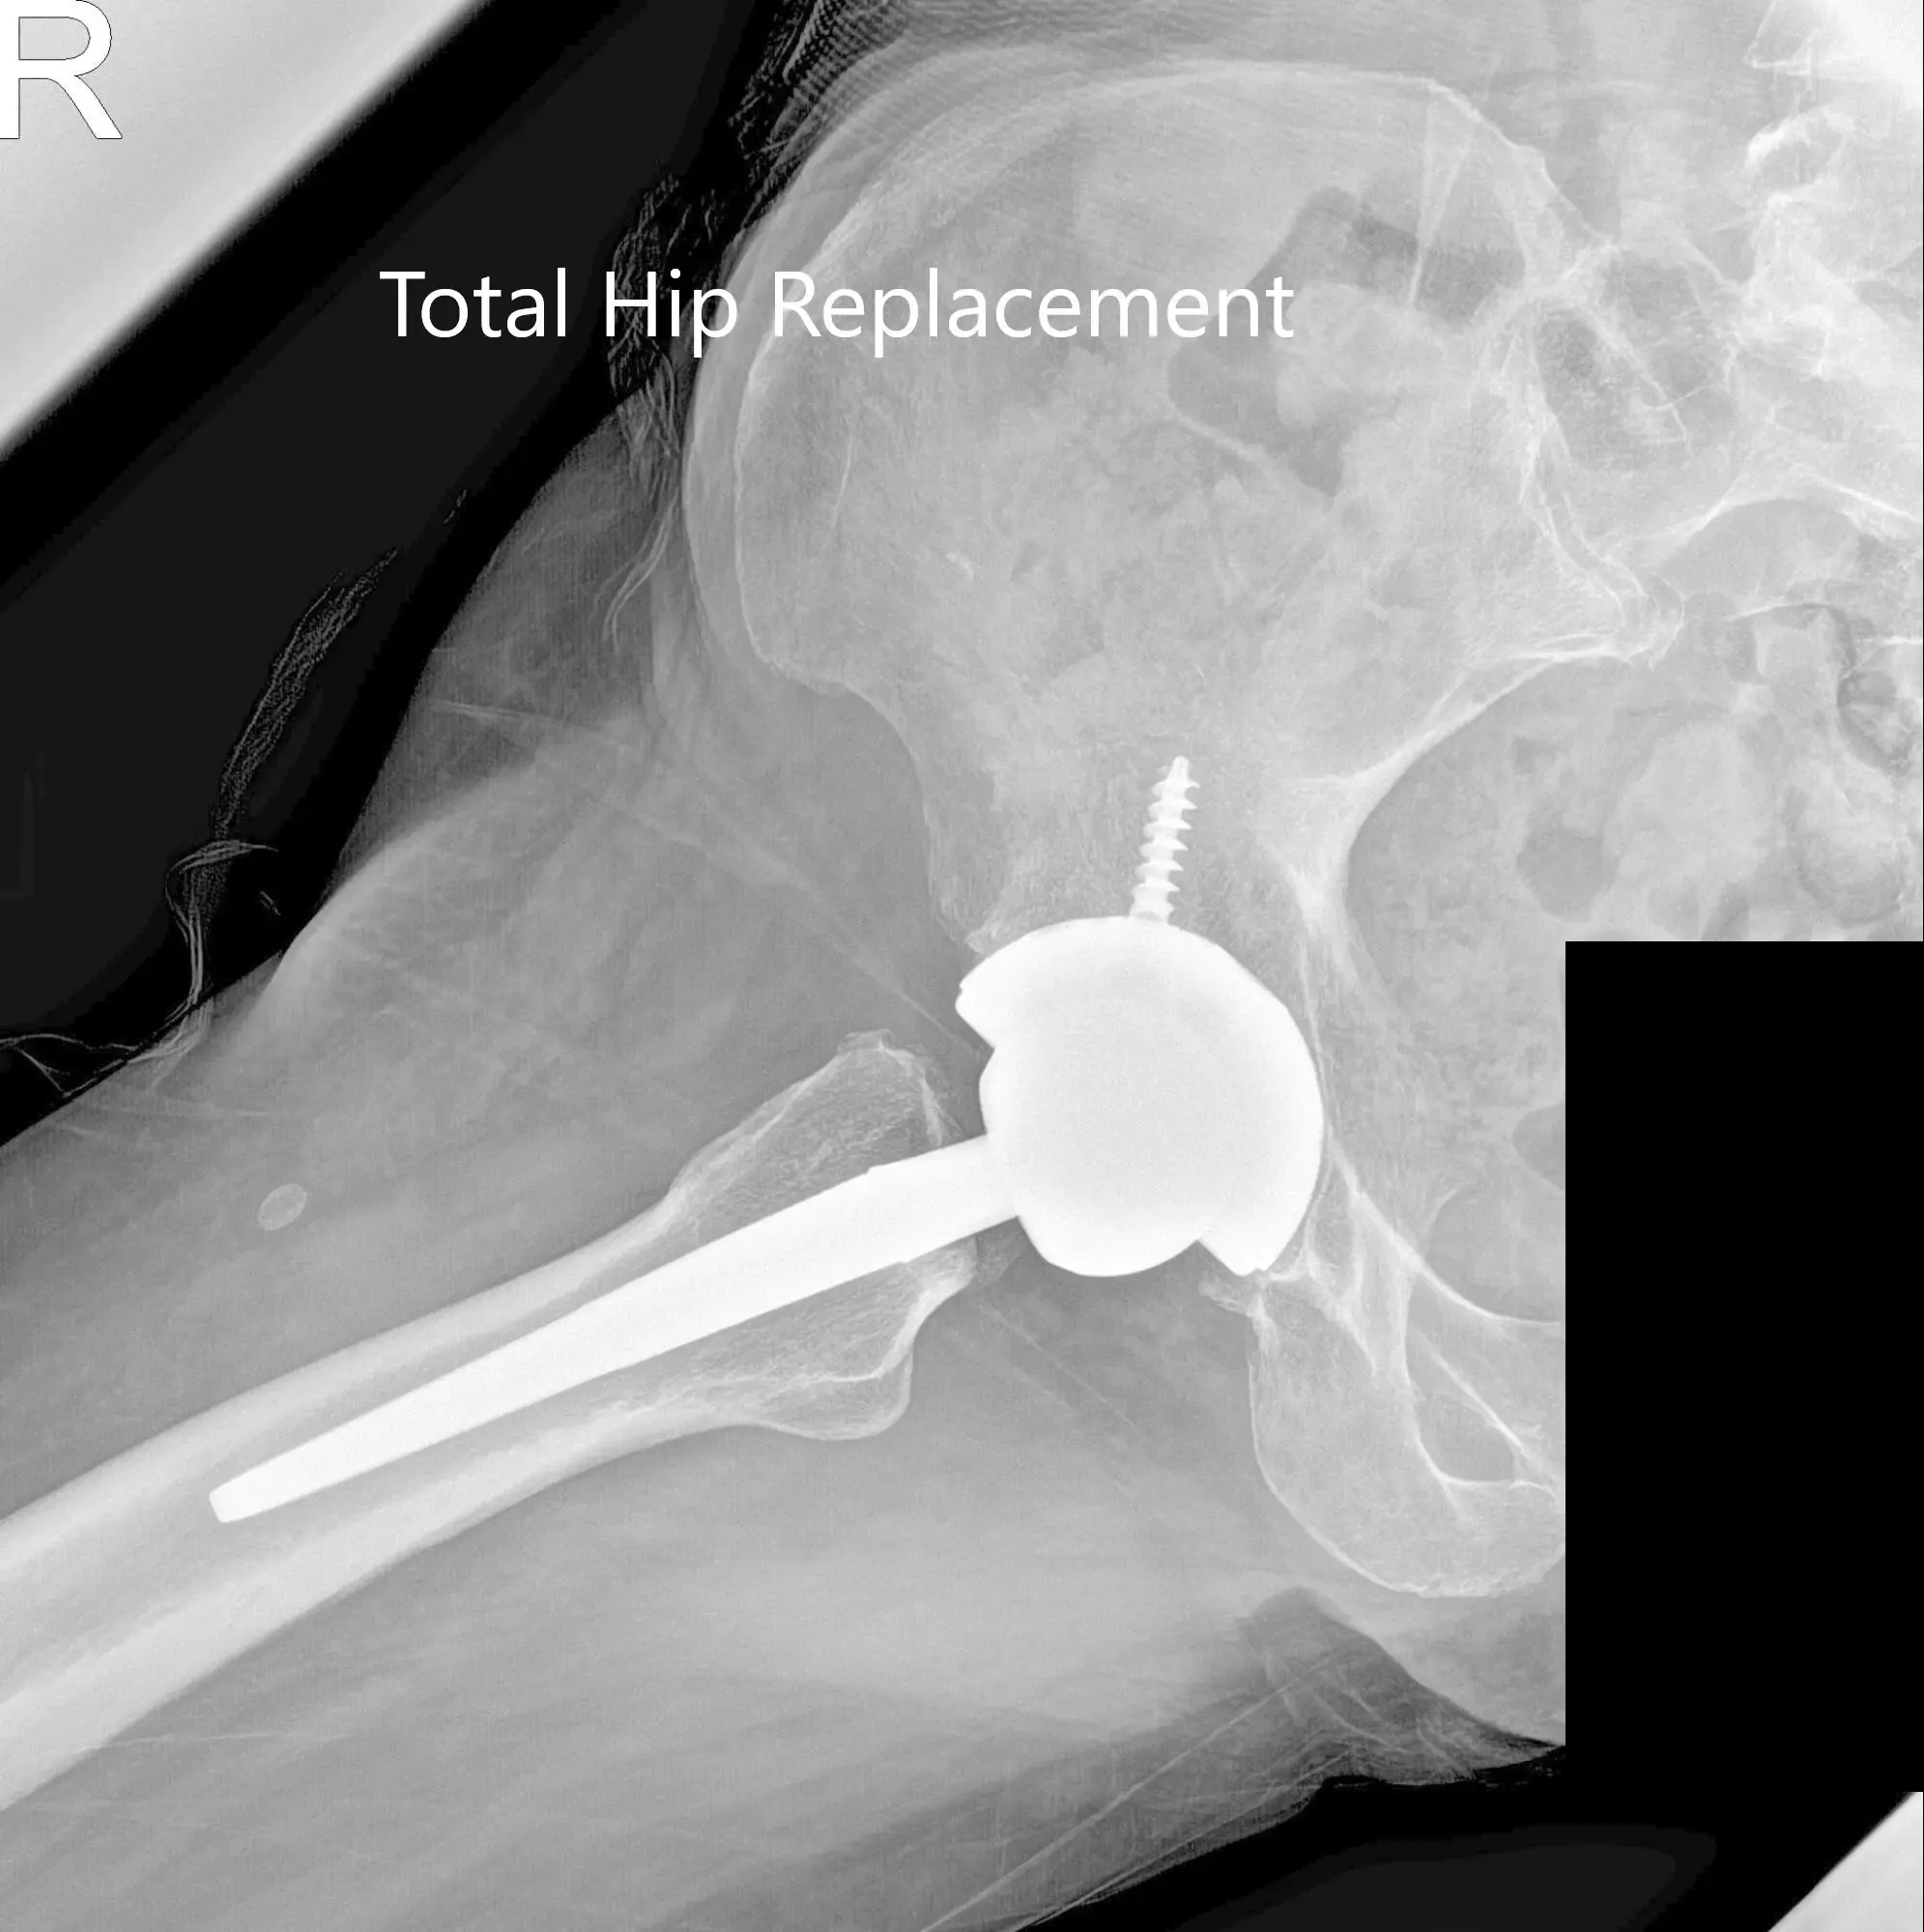

The patient returned for a total hip replacement of the left side two months later. He was enthusiastic about the success of the right hip arthroplasty. He underwent a left total hip replacement with an acetabular shell of 52 mm and a 0-degree polyethylene insert. Additionally, a 6.5 mm x 25 mm cancellous screw was used for fixation. A ceramic head of 36 mm was used with a127 degree angle hip stem (stem length – 102 mm and neck length -30 mm).

Postoperative X-ray of the left hip showing AP and lateral views.